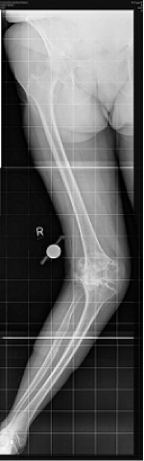

A 76 year old woman presented with a painful, valgus right knee which had progressively worsened over past 2 years. On clinical examination she had a marked valgus deformity of her right knee measuring 49° using a goniometer. Range of motion on examination was measured to be 5° to 100° with an extensor lag of 15°; the valgus deformity was not correctable on clinical examination. Radiographs confirmed a massive valgus deformity of the right knee with a bony defect in the lateral femoral condyle and lateral tibial plateau (Figure 1–3). The patient was consented to have a simultaneous peri-articular femoral osteotomy and total knee arthroplasty procedure in order to address the severe valgus deformity and osteoarthritis. The patient was informed that the data concerning her case would be submitted for publication and an informed consent obtained. Pre and post operative WOMAC and VAS scores were obtained.

Figure 1 Preoperative AP view of the knee.

Figure 2 Preoperative lateral view of the knee.